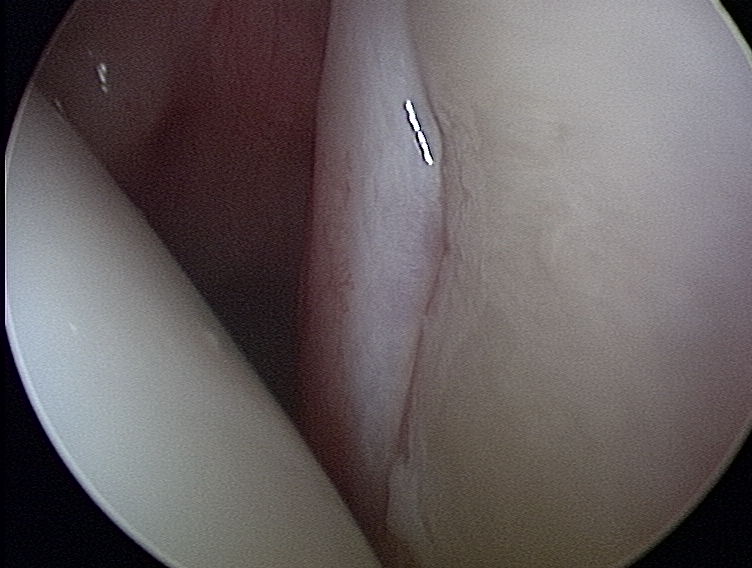

Tutaj widoczny jest obrąbek stawowy z panewką ( patrzymy od tyłu na przednią cześć panewki) bez zmian, z lewej główka kości ramiennej.